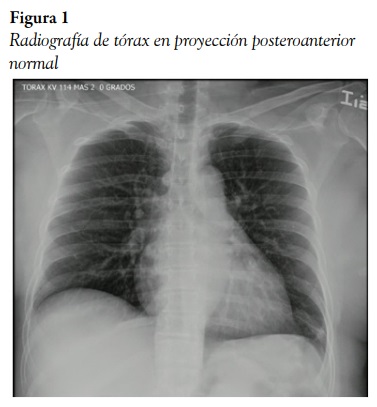

En la revisión primaria no se le identificaron lesiones potencialmente fatales. Respecto a la revisión secundaria, se encontró a la mujer hipertensa (TA: 140/79 mmHg), polipnéica (FR: 26 r.p.m.) e hipoxémica (saturación: 85%; FiO2: 21%), y con frecuencia cardiaca normal (87 l.p.m.). En la auscultación, se documentaron crépitos en la base pulmonar derecha, dolor a la palpación de los primeros arcos costales posteriores derechos, y normal en el resto del examen físico. Se solicitó tomarle creatinina, que reportó ser normal; hemograma, que mostró leve leucocitosis (11.000/dL); gases arteriales, que indicaron un trastorno moderado de la oxigenación (PaFio2: 210 mmHg/%) sin trastorno de la ventilación, y radiografía de tórax posteroanterior, que fue normal (figura 1).